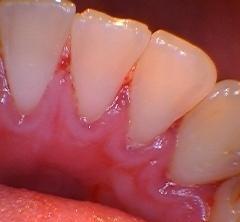

Does your gum bleed easily every time you brush your teeth?

You may be confused you could just get regular cleaning for these build-ups. You will need gum treatment or Scaling and Root Planning to remove all these for healthy gum!